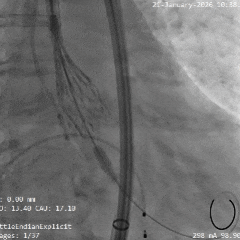

术中影像

根部造影

瓣叶活动差,可见明显反流,猪尾导管测量跨瓣压差约50mmHg

20mm球囊预扩

微腰微漏,左右冠均显影

造影确认瓣环与瓣膜位置

瓣膜0位初始定位释放,展开过程微微下移

全展开位造影评估

瓣膜呈直筒型,微腰,大弯侧约瓣下3mm,少量反流,冠脉显影

瓣膜无张力脱钩

植入后造影评估

瓣膜位置合适,可见少量反流

多角度造影评估

瓣膜形态可,冠脉显影,猪尾测量压差为0